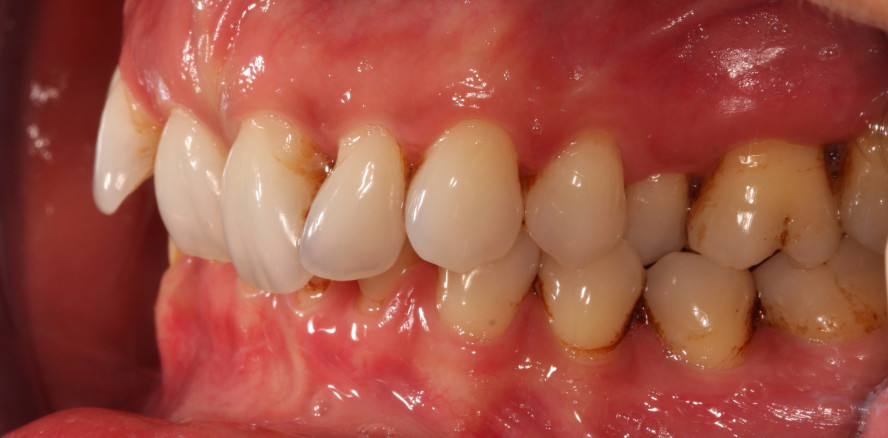

Der extraorale Befund war unauffällig. Es lagen keine Schwellungen oder Asymmetrien vor. Es handelte sich um ein parodontal erkranktes Gebiss. Weisheitszähne waren nicht vorhanden. Die Zähne wiesen Rotationen in beiden Kiefern auf. In der Front kam es infolge der parodontalen Erkrankung zu einem Flairing. Zudem hatten sich interdentale schwarze Dreiecke gebildet. Es zeigten sich deutliche Rezessionen im Front- und Seitenzahnbereich. Außerdem war ein leichter Foetor ex ore feststellbar. Was den dentalen Befund anbelangt, so handelte es sich um ein konservierend suffizient versorgtes Erwachsenengebiss mit multiplen Kompositfüllungen (an 17, 16, 15, 12, 22, 25, 26, 27, 37, 36, 35, 44, 45 und 47). Alle Zähne reagierten positiv auf den Kältetest. Die Zähne 14, 12–22, 24, 31–41 wiesen einen Lockerungsgrad I auf.

Die Mundhygiene der Patientin war nicht gänzlich suffizient. An vielen Zahnflächen waren weiche Beläge sowie Zahnstein sichtbar. Der BOP-Index (Bleeding on Probing) betrug 66 Prozent und der PCR (PlaqueControl Record1) 33 Prozent. Die Sondierungstiefen waren generalisiert erhöht, und es kam bei der Sondierung zu deutlichen Blutungen. Der PSI betrug „3–4“ in allen Sextanten. Der dentale Befund kann der Abbildung 1 entnommen werden. Der Fotostatus vom 1.3.2017 ist in Abbildung 2 dargestellt.

Die kieferorthopädische Behandlung des Oberkiefers begann am 18.9.2017. Eine Behandlung des Unterkiefers war nicht gewünscht. Es wurden selbstligierende Brackets aus Keramik eingesetzt, und die Patientin wurde über die zusätzlich notwendigen Hygienemaßnahmen aufgeklärt. Die Bogenfolge wurde alle acht Wochen wie folgt festgelegt: 0.14 NiTi, 0.16 NiTi, 0.18 NiTi, 0.20 NiTi, 0.20 Stahl. Es wurden keine Vierkantbögen verwendet, um einem übermäßigen Wurzeltorque zu verhindern. Abbildung 10 zeigt die Situation zu Beginn der kieferorthopädischen Behandlung. Abbildung 11 zeigt den Behandlungserfolg der Intrusion nach drei Monaten. Am 5.6.2018 wurde die kieferorthopädische Behandlung beendet. Die Brackets wurden entfernt und die Zähne professionell gereinigt. Nach der Behandlung waren nach wie vor interdentale schwarze Dreiecke zu erkennen, die mittels Kompositrestauration verschlossen werden sollten. Abbildung 12 zeigt die Situation vor der Restauration mit Komposit. Die Front wurde erfolgreich intrudiert.